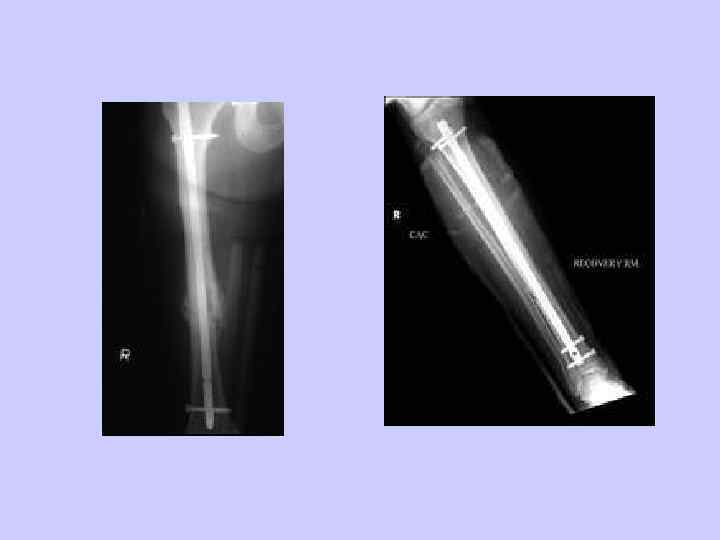

Внутренняя фиксация • Пластины и винты • спицы (Kirschner) • Внутрикостные стержни

Так мы и работаем • Распознать и оказать первую помощь • Снимочки (спасибо, Вильгельм!) • репозиция • стабилизация- гипс, синтез – погружной/чрезкостный • реабилитация